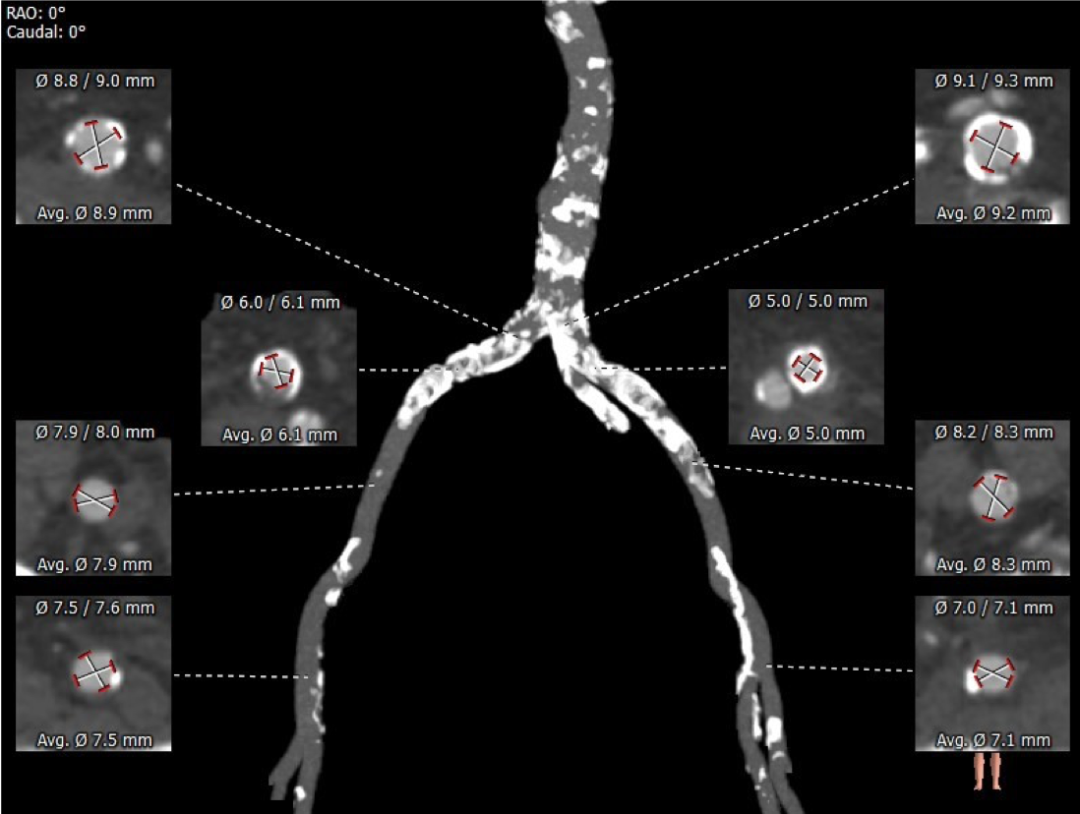

主动脉根部评估

CT 数据显示该患者为三叶式主动脉瓣

血管外周入路评估

腹主下段、双髂总附近多发钙化,部分截段钙化呈环状分布,血管内径受限,双侧股动脉穿刺点周围少量附壁钙化。